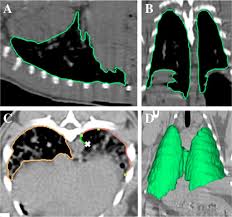

A Computational Pipeline For Quantification Of Pulmonary Infections In Small Animal Models Using Serial Pet Ct Imaging Ejnmmi Research Full Text